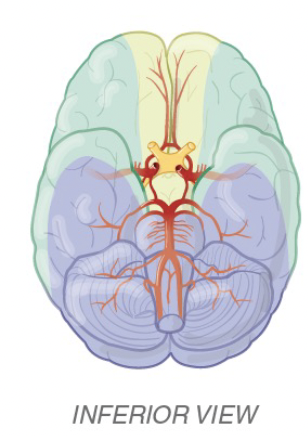

Cortical strokes most commonly affect vessels in [order]

Cortical strokes most commonly affect MCA > PCA > ACA

22

ID the vessels